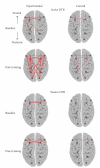

Neuro-electrophysiological studies on meditative breathing revealed its association with either a relaxed or an attentive state. The present study aimed to investigate whether the Shaolin Dan Tian Breathing (DTB) technique, which consists of the Passive and Active subtypes and can be considered as a relaxation exercise and Qigong, would induce both relaxed and attentive states. Twenty-two adults and 22 age-, gender- and education-matched controls received training on the Shaolin DTB (experimental group) and the progressive muscle relaxation respectively for one month. Eyes-closed resting EEG data before and immediately after each type of breathing were obtained individually at baseline and after one-month training. At baseline, the EEG changes after the Shaolin DTB between both groups were comparable. After one-month training, participants in the experimental, but not the control, group showed enhanced temporal alpha asymmetry (an index of relaxation and positive mood) after performing the Passive DTB for five minutes, and enhanced intra- and inter-hemispheric theta coherence (an index of attention and alertness) after performing the Active DTB. The present findings suggested a positive effect of the Shaolin DTB technique on enhancing human neural activity and connectivity, which may possibly enhance mood state and cognitive functions.